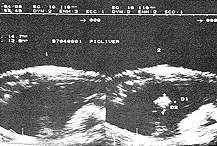

2、HIFU治疗后彩超检测与病理改变 HIFU照射后即刻靶区回声明显增加(图3),解剖大体观:靶区中央可见灰白色凝固性坏死,其周围见暗红色充血区,再外围为苍白色反应带,光镜下可见细胞不可逆性变性坏死。HIFU后1天彩超靶区血供消失、回声增强、边界不太清晰;病检:肝内微血管内皮严重破坏,血管壁塌陷,肝板破坏,肝细胞核固缩。3~7天,靶区回声仍增强,边界清晰,内无血供(图4);病检:靶区呈灰白色改变、质硬、与周围组织界线清晰。光镜下:靶区肝细胞大片坏死,与周围组织分界清楚,在分界处出现炎性细胞、坏死区微小血管破裂。第14天,彩超回声强弱不均,损伤体积缩小;病检:靶区开始收缩、坏死区周围有大量纤维母细胞和新生毛细血管增生。第21天,彩超:体积明显缩小,内部回声以低回声为主;病理:凝固性坏死组织逐渐液化吸收,剖面可见多个或单个小囊腔,壁薄而光滑,内为豆渣样坏死肝组织或清亮液体,镜下见:致密的纤维组织包囊坏死区,并见有大量淋巴细胞浸润。第28天,彩超下损伤区与正常区交界处无显著差异(图5);病检:大体损伤区明显缩小,损伤区基本为新生组织所代替,质地基本与正常肝组织相同,镜下:靶区中心,细胞坏死、自溶,结构完全被破坏,其周边区见假小叶生成,再外围为新生的肝小叶肝细胞形态与排列趋于正常。彩超测定体积与解剖所测损伤区体积基本一致。

损伤区回声增强,边界清晰

图4 在体猪肝HIFU损伤后72h声像图